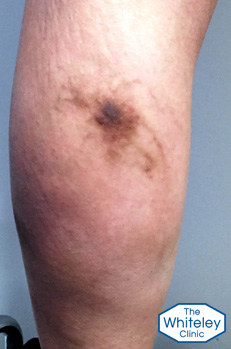

As can be seen by the pictures, the legs look relatively normal when viewed from the front. However there are two very brown areas on the outside of the left calf, with a very dark brown stain on the left calf muscle at the back.

Brown staining (haemosiderin) due to old phlebitis

The dark brown stains on the legs come from a complication called "phlebitis".

In veins that have become varicose, the blood does not flow in the normal direction. Therefore, in some patients the blood clots. When this happens in veins near the surface, the blood clot or "thrombus" inflames the vein and the overlying skin.

This inflammation causes the area to go red and lumpy in the short term. However as this settles down, iron in the blood caught in the thrombus leaches out into the skin. Because iron is toxic to the skin, the body surrounds the iron with protein following a brown pigment called haemosiderin.

Whilst the varicose veins remain, phlebitis will keep occurring causing further brown staining. In areas where there is already brown staining, even darker brown pigments will appear.

The only treatment for this is to treat the underlying problem first, preventing any more phlebitis, and then the brown staining will slowly settle.